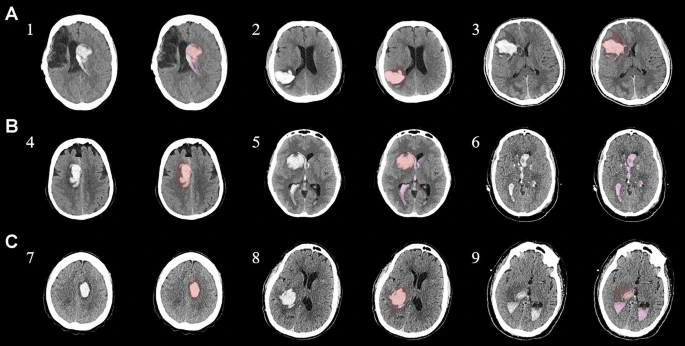

本研究納入2018年1月1日至2020年10月31日發(fā)病168小時內(nèi)發(fā)生急性ICH的患者。間充質(zhì)干細胞被靜脈注射給9名患者(5名女性,4名男性),平均年齡(范圍)為61(36-84)歲。表1總結(jié)了人口統(tǒng)計學(xué)和臨床??特征 。出于描述目的,患者按照入組順序獲得編號,并連續(xù)分配到三組中的一組,每組三人。根據(jù)模型 2 分割,ICH體積范圍為0.1至54.9mL(平均ICH體積為23.5mL)。5例ICH累及局部腦葉,其余則位于基底節(jié)或外囊深處。在三名患者中,ICH位于丘腦(圖1),在一名患者中,血腫位于多個腦結(jié)構(gòu)(即尾狀核、殼核和蒼白球)。平均而言,MSC在ICH后3天進行注射。